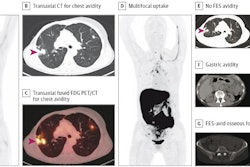

PET scans with an F-18 FES-PET radiotracer can reveal the target for therapy, as well as whether the therapy is working in patients with HER2-positive breast cancer. Image courtesy of David Mankoff, MD, PhD.The first role PET plays is helping to determine whether the cancer target is present.

One challenge using PET imaging with targeted tracers like FES is determining how homogenous the cancer may be, Mankoff added. In other words, the approach may not visualize differences between tumors of the same type in different patients. In this regard, he said that dual imaging with F-18 FES and FDG, a standard and more general imaging tracer, may be effective, he said.